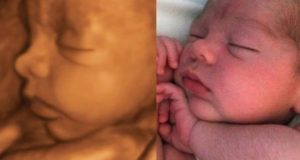

Если родители решают делать четырехмерное узи на 30-32 неделе беременности, то у них появится возможность рассмотреть в объемном цветном изображении все черты лица ребенка.

Увидеть, как он улыбается, зевает, хмурится. Лицо становится выразительным, и можно различить уже носик, щечки и губы.

Для родителей, конечно, это будет незабываемый момент в их жизни, особенно если сделать видеозапись на диск.

4Д УЗИ на 30 неделе во время беременности и после рождения